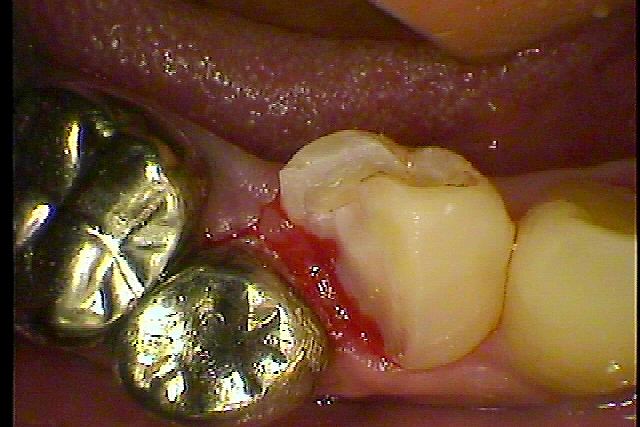

右下4番の根管治療になります 2根管あってかなり珍しいです|お知らせ |広島市安佐南区の歯科医院 右下4番の根管治療になります 2根管あってかなり珍しいです トップ お知らせ・ブログ お知らせ 右下4番の根管治療になります 2根管あってかなり珍しいです 右下4番の根管治療になります 2根管あってかなり珍しいです この歯が痛むとのこと 大きな虫歯になっています 神経は感染を起こし、膿んでいました 中は大きな虫歯になっていました 根管治療を無麻酔で行いました 1根を先に根充しています 2根目も根充を行いました CRにて土台を建ててインレーの型取りを行っていきました Web診療予約 初めての方へ 選ばれ続ける理由 院内設備について 歯が痛いしみる一般歯科 歯がぐらぐらする歯周病 健康な歯を保ちたい予防歯科 子供の虫歯予防をしたい小児歯科 銀歯をセラミックに審美歯科 白い歯を目指しませんか?ホワイトニング 矯正専門医がいるので安心矯正歯科 抜けた歯を補いたいインプラント・入れ歯 医院案内 スタッフ紹介 メリィハウス歯科クリニックオフィシャルホームページ ラベンダー歯科クリニックオフィシャルホームページ お知らせ・ブログ ホーム 診療科目 一般歯科 歯周病治療 予防治療 小児歯科 審美治療 ホワイトニング 矯正歯科 入れ歯・インプラント マウスピース矯正 初めての方へ 院長・スタッフ 設備紹介 医院案内・アクセス メニューを閉じる